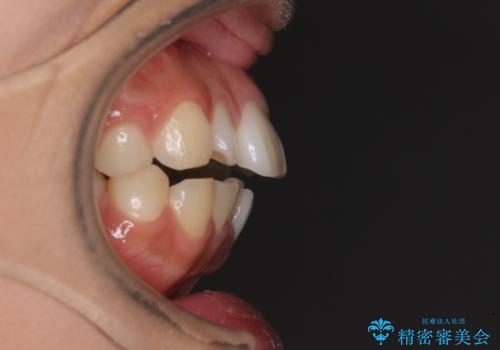

- 出っ歯と口の閉じにくさ、デコボコを気にして来院された患者様です。

口元の突出感を改善するため、上下左右第一小臼歯4本の抜歯を行い、ワイヤー装置による矯正治療を行うこととしました。

舌の突出癖により上下前歯は非接触であり、非常に前方に飛び出している状態でした。

舌のトレーニングをしっかりと行っていただき、口の閉じやすい歯並びに仕上げることができました。